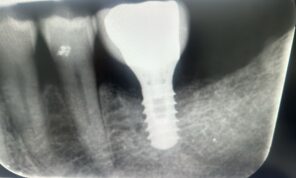

Hieronder laten we een perfecte casus zien van een verontreinigd implantaatoppervlak dat is glad gemaakt met behulp van NiTi brushes en Perisolv. Daarna is er opgebouwd met hyaluronzuur, smartgraft en een membraan. Tot slot heeft de behandelaar het geheel twee maanden laten genezen met een healing abutment. De resultaten op de foto's hieronder spreken voor zich.